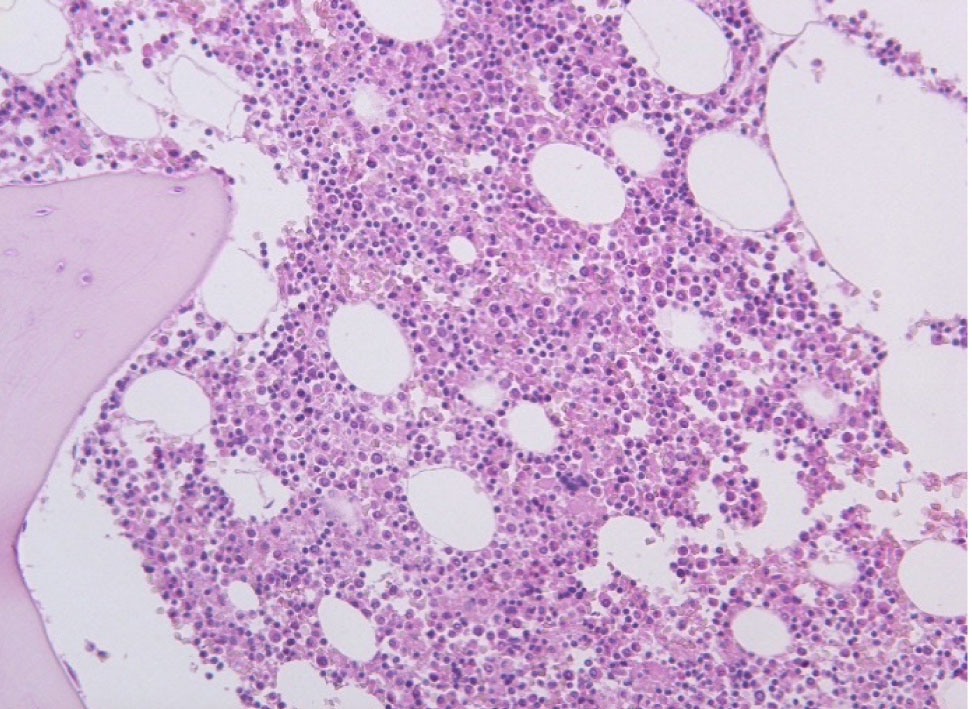

Рис. 1. Амилоид в строме и стенке сосудов сердца. Окраска гематоксилин-эозин, ×100

Гистологическое исследование. Сердце – кардиомиоциты гипертрофированы, диффузный кардиосклероз. При окраске на амилоид в строме и стенке сосудов отложение амилоидных масс (рис. 1). Селезенка – красная пульпа полностью замещена однородными массами, дающими положительную окраску на амилоид (рис. 2).